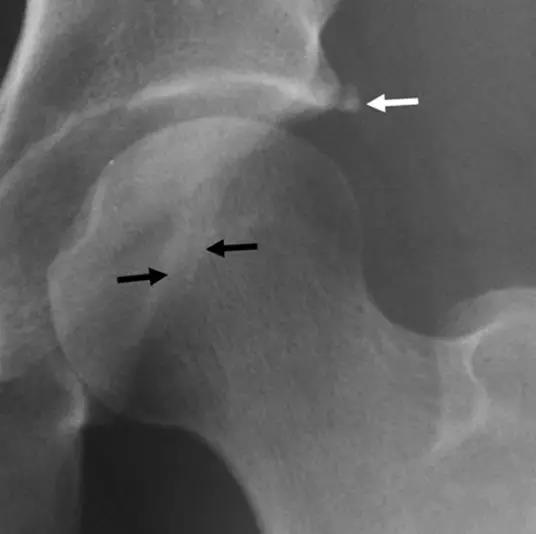

凸轮撞击型FAI▼

- 股骨头颈间的凹陷不足,伴局部的骨质增生。

- 股骨头颈的“ 枪柄样” 畸形。

- 股骨头颈联合处前上缘骨性突起。

- 非圆形的股骨头。

- 股骨头颈联合处前缘骨性突起、骨质硬化,α角增大。